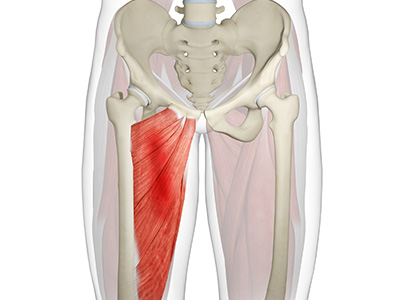

- Adductors: These muscles are located in the thigh which helps in adduction, the action of pulling the leg back towards the midline.

- Rectus femoris: This is the largest band of muscles located in front of the thigh. They also are hip flexors.